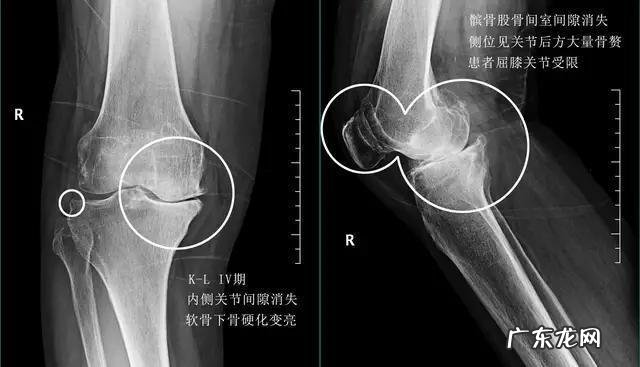

老人出现膝关节骨关节炎后还能锻炼吗?关节炎是很多老人经常谈及的一个疾病,有时老人之间唠嗑,谈到某一位老人膝盖疼的话,其他人都会问:“你是不是关节炎了?”,其实关节炎可以说是多种疾病的统称,包括骨关节炎、痛风性关节炎、风湿性关节炎以及类风湿性关节炎等等很多的关节炎都可以归类为关节炎这三个字,日常生活当中很多老年人口中的所谓关节炎,其实应该是骨关节炎 。骨关节炎主要的病理基础是关节内的软骨磨损、退变而导致关节出现骨质增生、骨刺的形成 。

因为当关节内的软骨发生磨损以后,骨与骨之间承受的压力就会有所改变,而我们的身体为了更好的减少骨头之间承受的压力,就会想方设法的增加骨头的面积,于是骨赘开始出现了,所以少量的骨质增生是帮助我们的,但如果软骨磨损的越来越重,骨赘也就是骨质增生形成的越来越多,刺激到了关节这边的组织就会导致各种各样的症状,病情严重的情况甚至会导致关节畸形,影响患者的膝关节的屈伸功能,造成长久的疼痛 。

症状:早期的膝关节骨关节炎患者往往会表现出膝关节后方的紧张感,在久坐或者是久站以后,膝关节有明显的不适,而疼痛并不是特别的严重,有些患者在夜深人静的时候屈伸膝关节是可以听到响声,但并不会有明显的痛感,在过度劳累的时候可能会出现膝盖的疼痛,但是休息以后就会有明显的减轻,另外还有很多老人会出现上下楼梯时关节的疼痛,但走平路往往非常正常 。诊断:早期的膝关节骨关节炎可以通过x线或者是核磁检查来明确诊断,当骨赘形成的不是非常多的时候,通过核磁检查可以早期的发现关节内是否存在软骨的磨损,从而进行早期的干预,比如口服氨糖等措施 。还能锻炼吗?在这个阶段是完全可以进行体育锻炼的,只是要注意运动的量和运动的时间,比如平时通过快走来锻炼身体,那么尽量要注意行走的步数,控制在8000到1万步就可以了,而且不要一次性走完,因为长时间的行走会造成关节周边肌肉、筋膜的紧张,会加重骨关节炎的病情,分次行走可以起到同样的运动效果,而且不会造成关节周边的负担 。另外游泳、打太极拳、骑自行车也都是可以的,同样注意量 。●中期的膝关节骨关节有什么样的症状,可以锻炼吗?